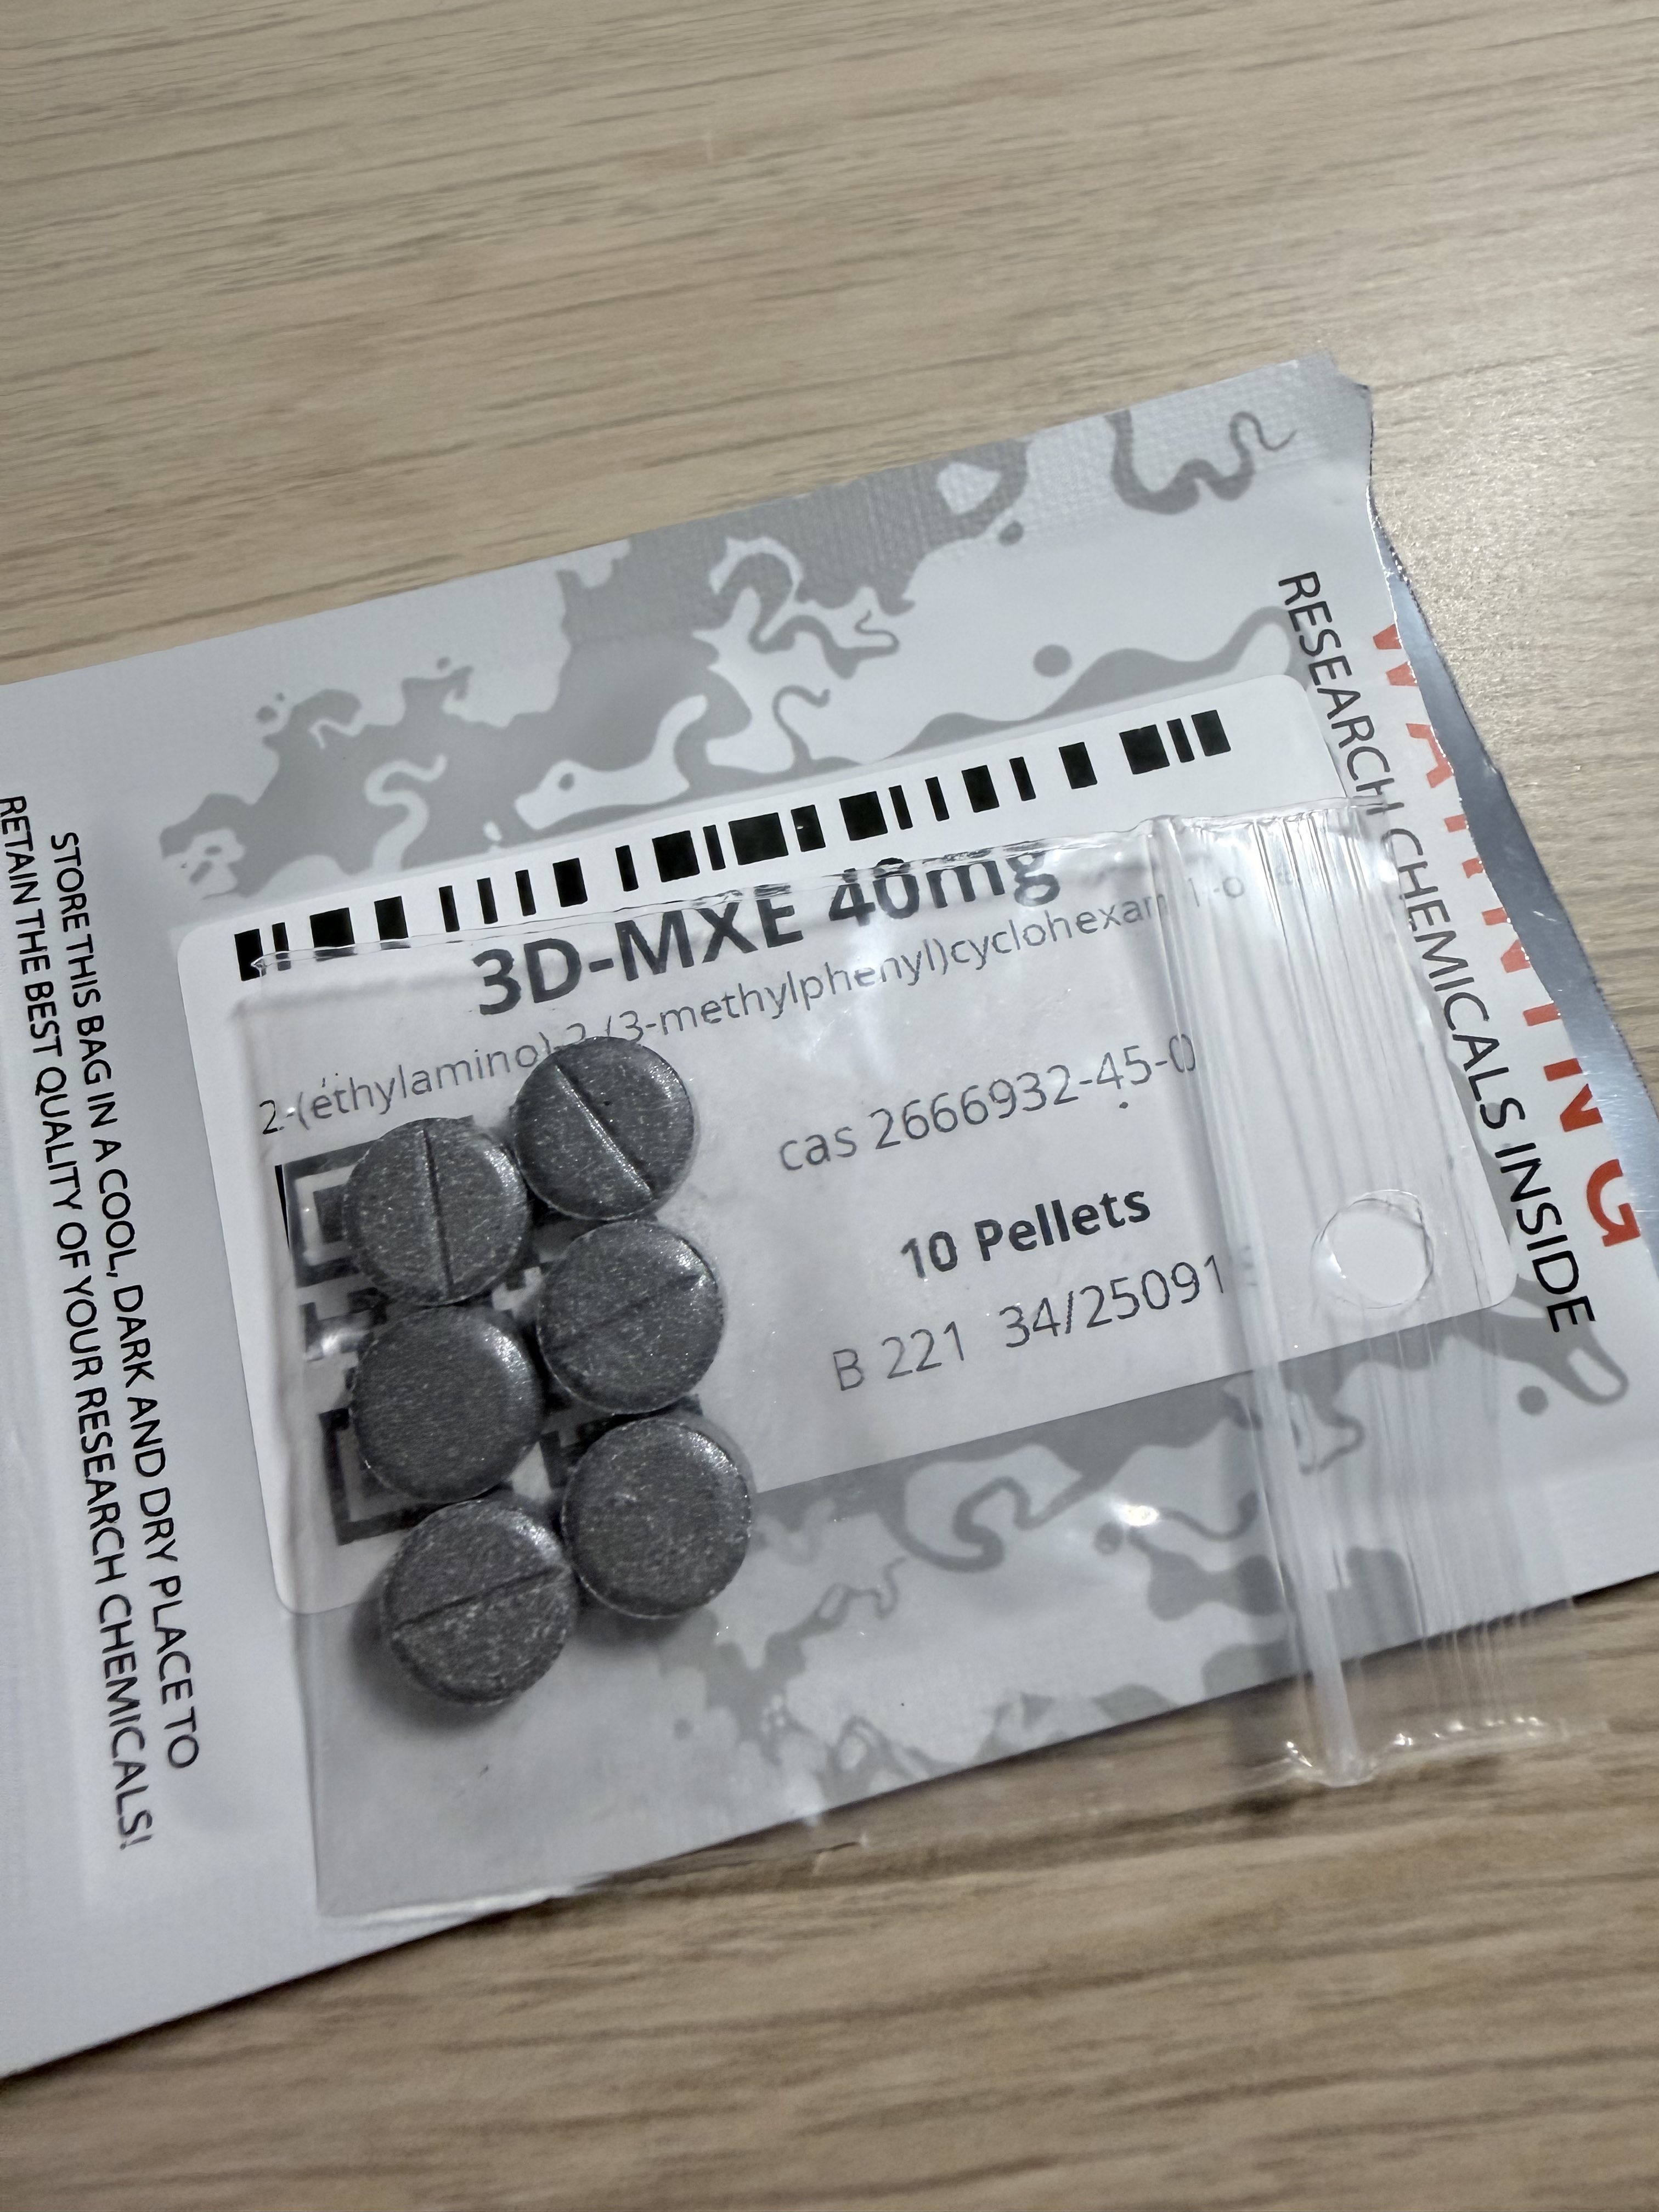

一款gaba-a物质的rp...

40mg舌下

全网都没什么使用报告,理论大概推了一下猜效果会比较像Amanita,多半没什么好事,但也没想到能直接掉线了()

其实重启过程的意外地和色胺ego death那次挺像,都有一种像信条里逆转世界的感觉,事物运行的规律很反常

总之不建议使用。虽然后面睡挺香的x https://t.co/rHJG6jnKz5